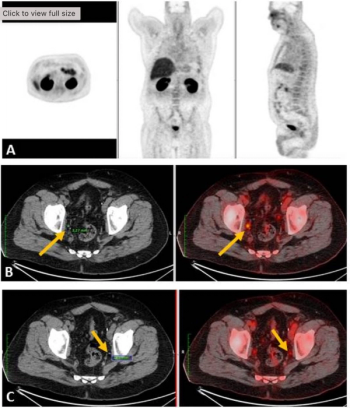

In a video interview, Hong Song, M.D., Ph.D., discussed retrospective research, presented at the recent Society for Nuclear Medicine and Molecular Imaging (SNMMI) conference, that evaluated the combination of artificial intelligence (AI)-based software and the PSMA agent piflufolastat F 18 to help quantify prostate cancer lesions and associations with biochemical progression-free survival.